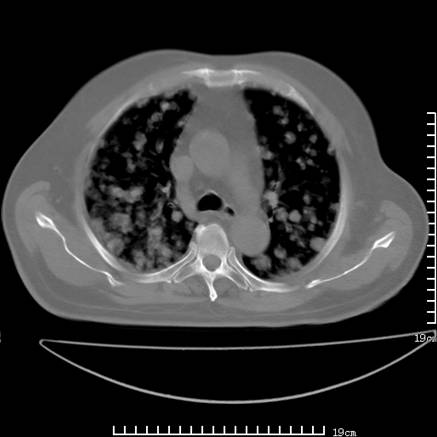

张男,75岁,干咳半年余,小便不利二年,b超检查前列腺增大,未见明显肿块;前列腺癌血生化检查多项指标明显增高。

双肺内多发转移瘤,纵膈淋巴结转移。来源前列腺?建议盆腔mri进一步检查。

双肺转移满了。

两肺广泛转移瘤。